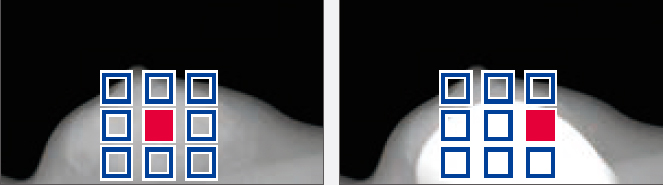

AMULET Innovality utiliza um detector de tela plana de conversão direta feito de selênio amorfo (a-Se) que exibe excelente eficiência de conversão no espectro de raios X mamográficos. O detector HCP (Padrão de fechamento hexagonal) coleta eficientemente sinais elétricos convertidos dos raios X para obter alta resolução e baixo ruído. Este design exclusivo possibilita a realização de uma DQE (Determinação do rendimento quântico) maior do que com a matriz de pixels quadrados de painéis TFT convencionais. Com as informações coletadas pelo detector HCP, a AMULET Innovality cria imagens de alta definição com um tamanho de pixel de 50 μm; o melhor disponível com um detector de conversão direta.

Pixel convencional quadrado

Pixel hexagonal do AMULET Innovality